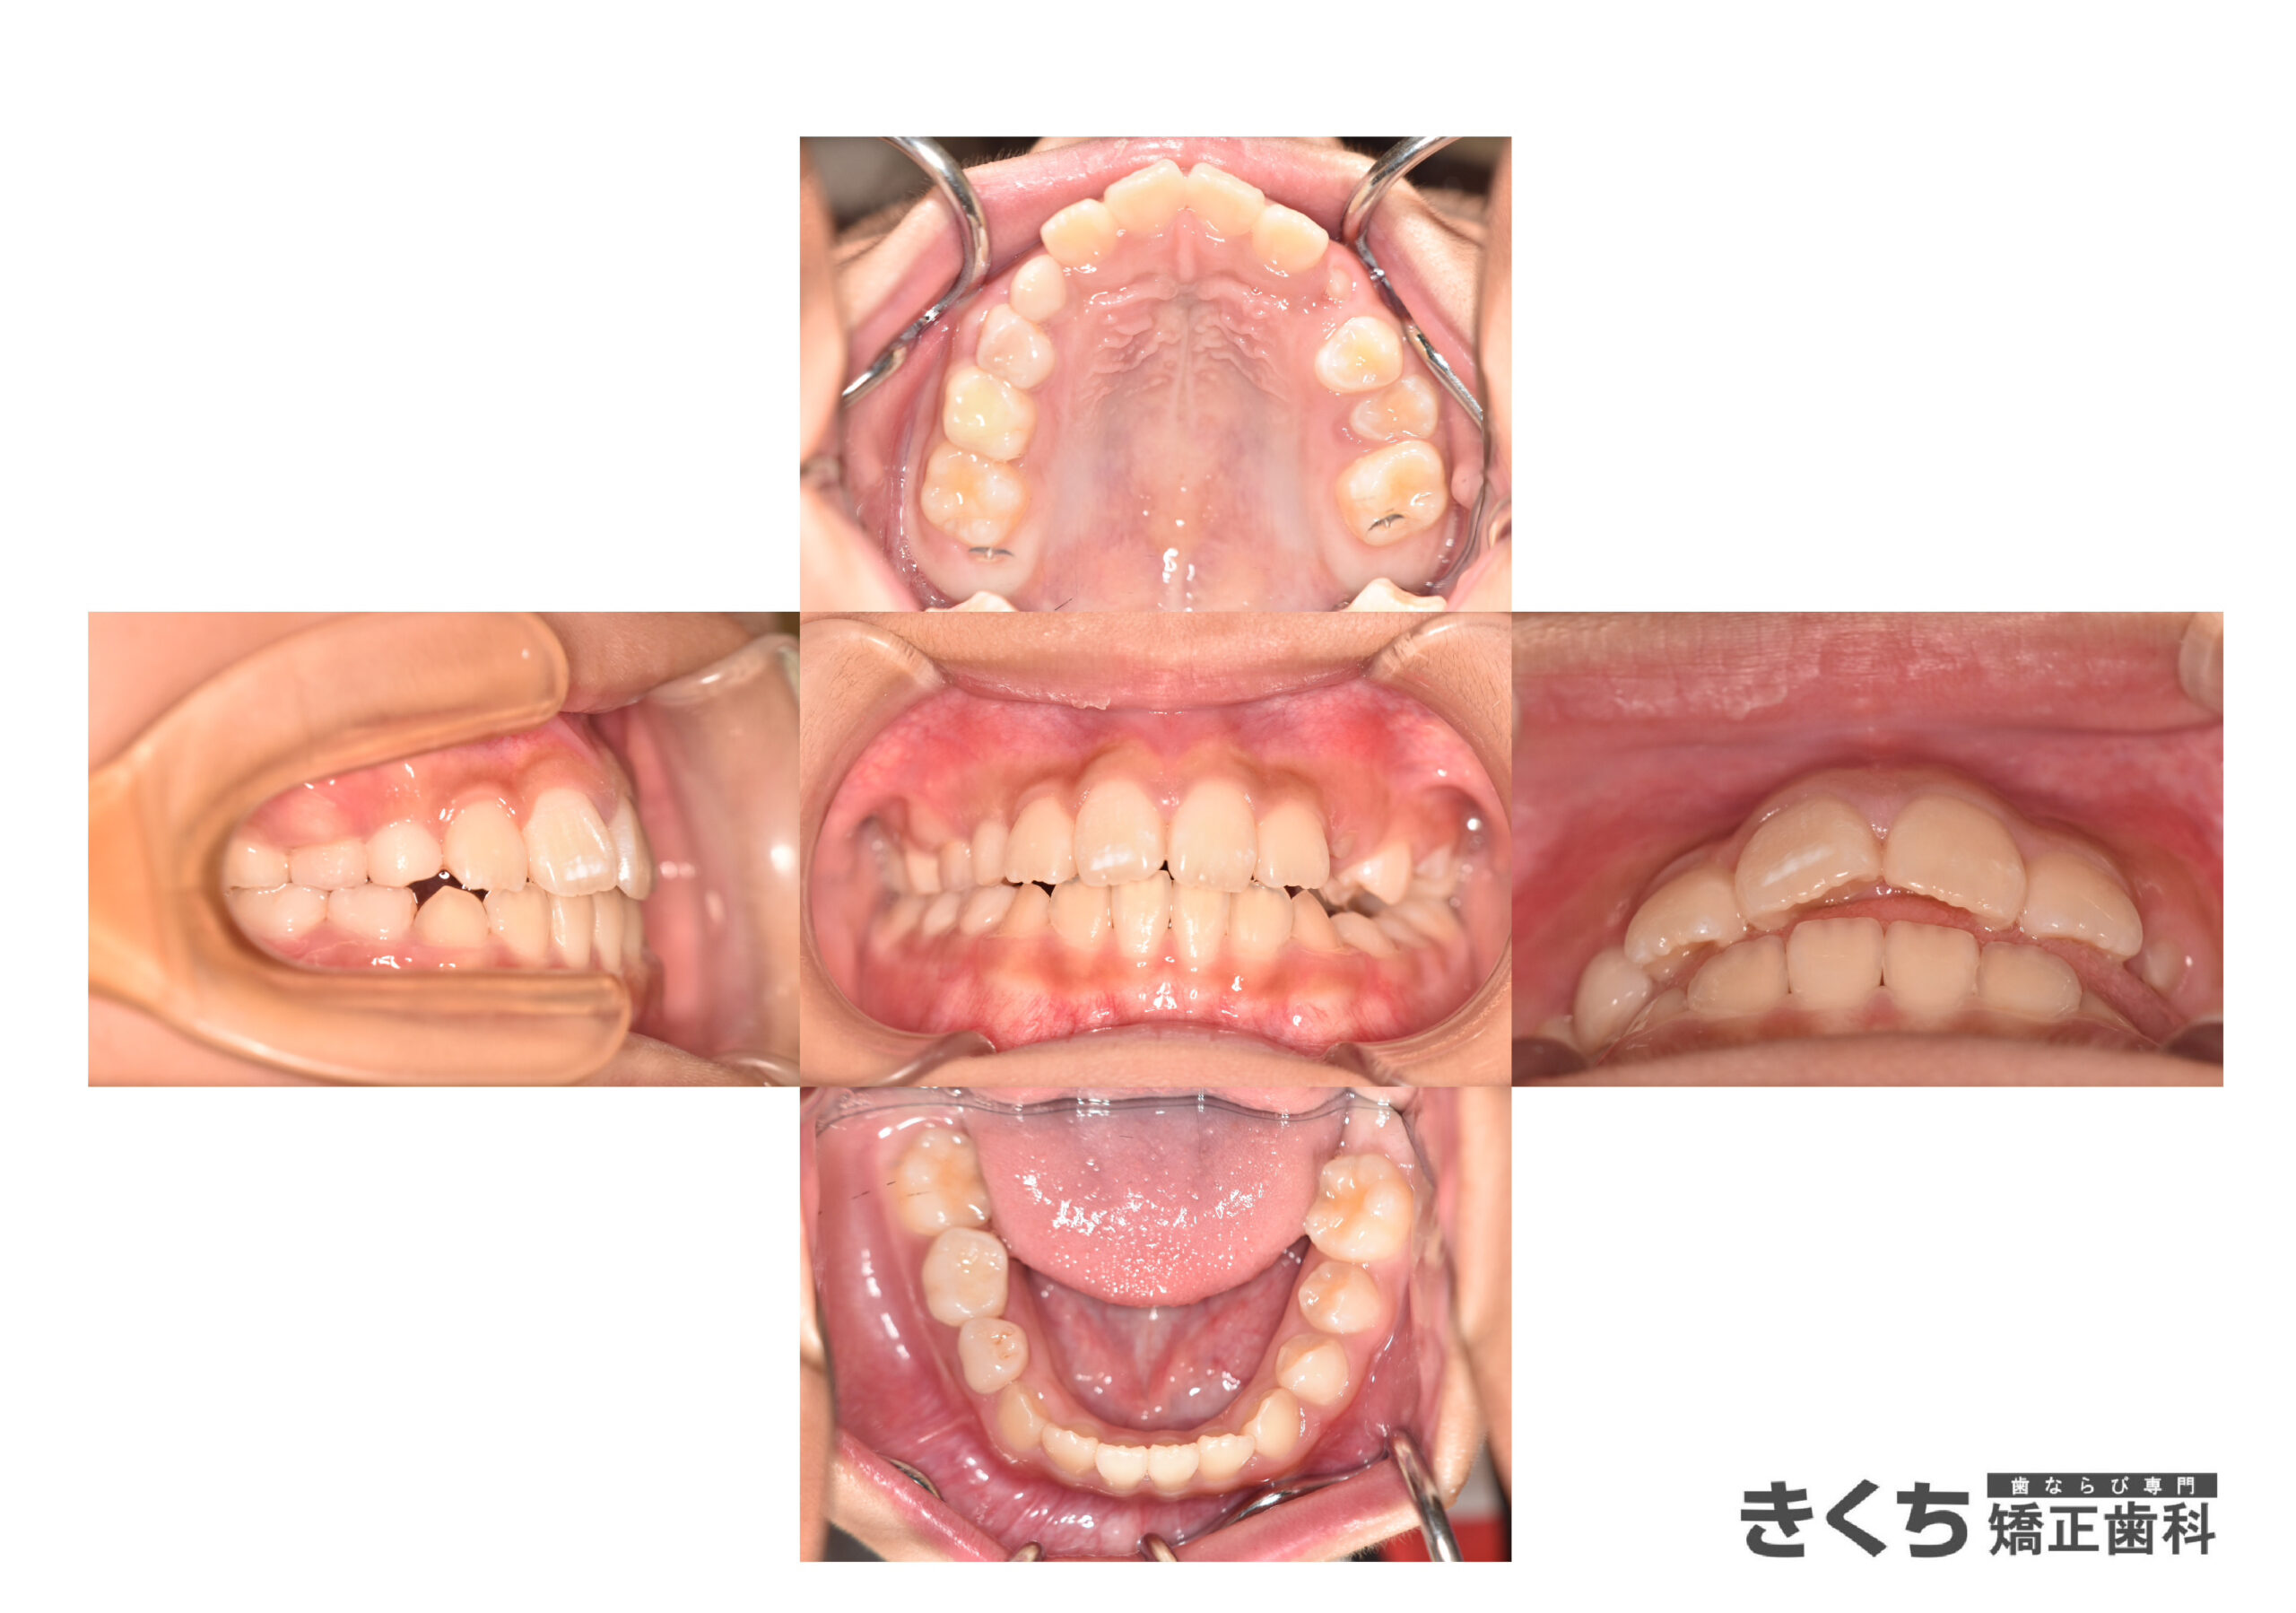

初診時9歳、かみ合わせを気にして来院

口呼吸、舌で上の前歯を押し出す癖がある

今すぐ矯正治療を始めたほうがいいと指摘を受けた

→6ヶ月ごとのペースで経過観察

口腔筋機能を改善するために指導を行いました。

↓↓↓↓↓↓↓ 6ヶ月後